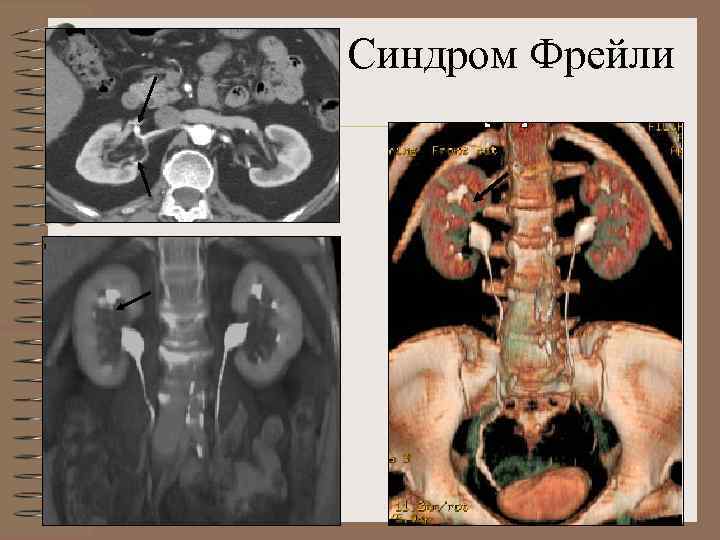

Изолированный гидрокаликс 9 мм Синдром Фрейли • Внутренний диаметр чашечки более 5 мм • Закругление свода • Сдавление шейки • Длительное контрастирование чашечки

Синдром Фрейли